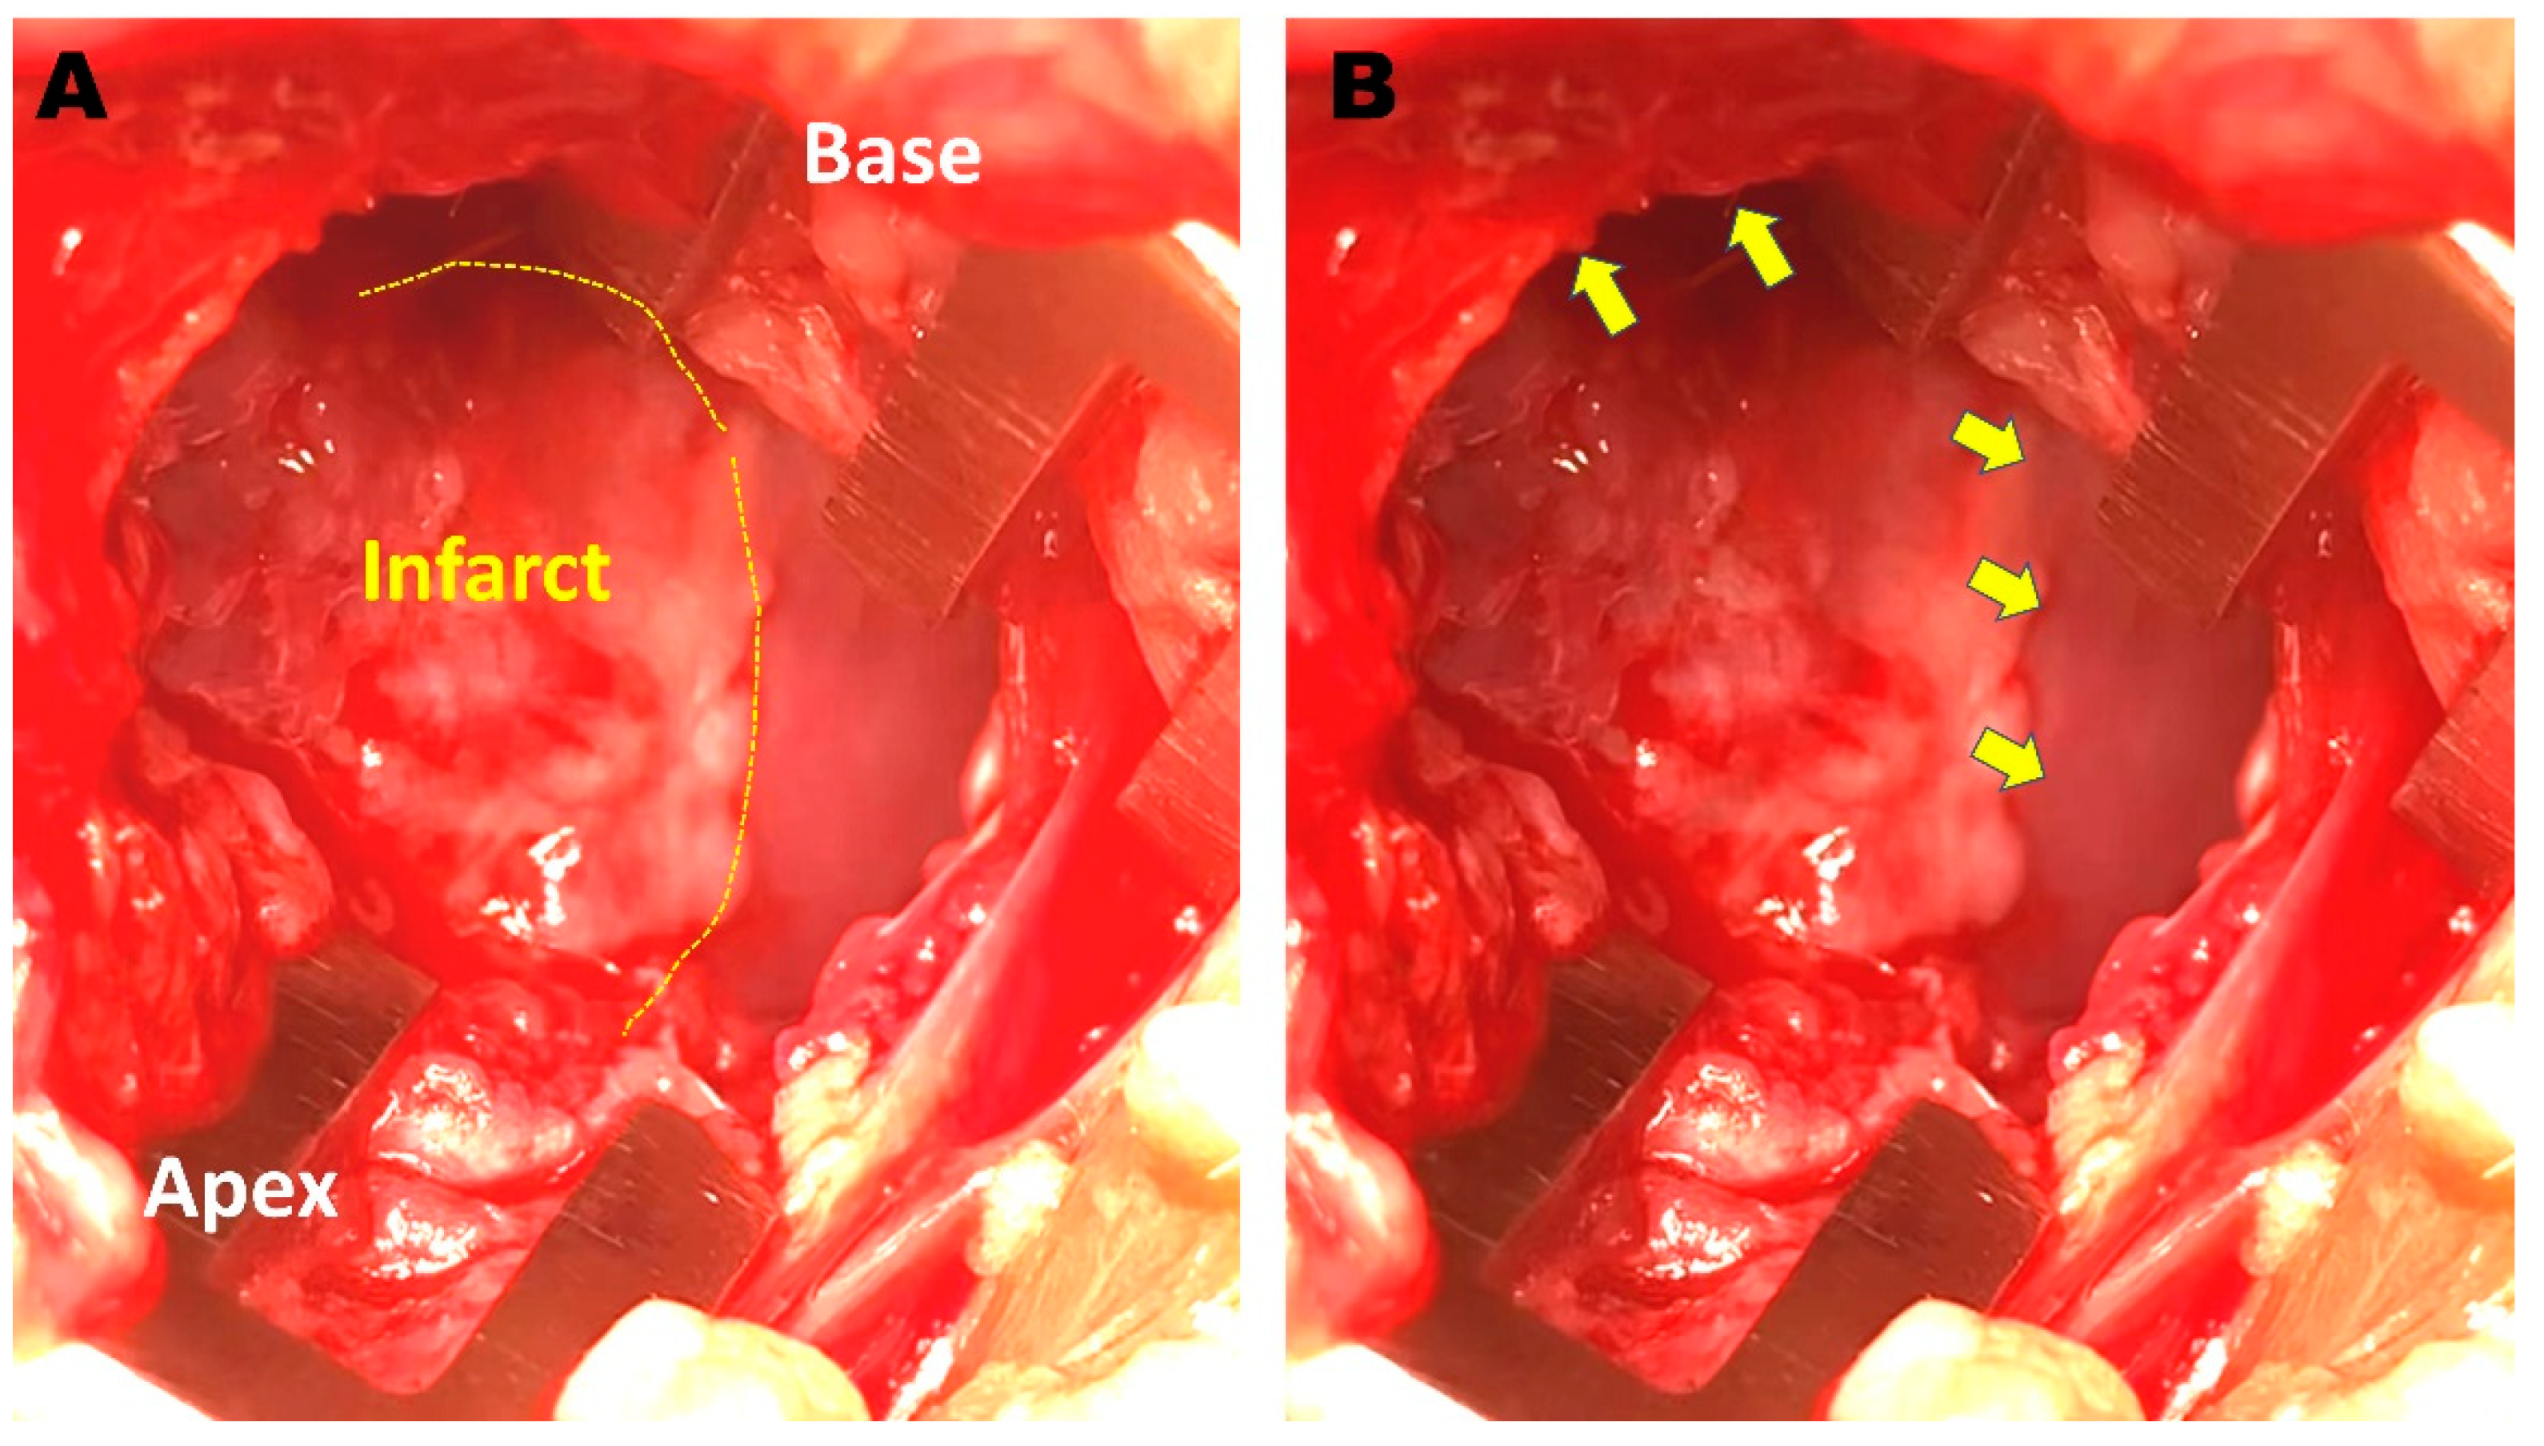

2.1. Creation of a Rabbit MI Model

2.5. Cell Injection and ILR Implantation

2.6. Repeated EPS and Histologic Examination